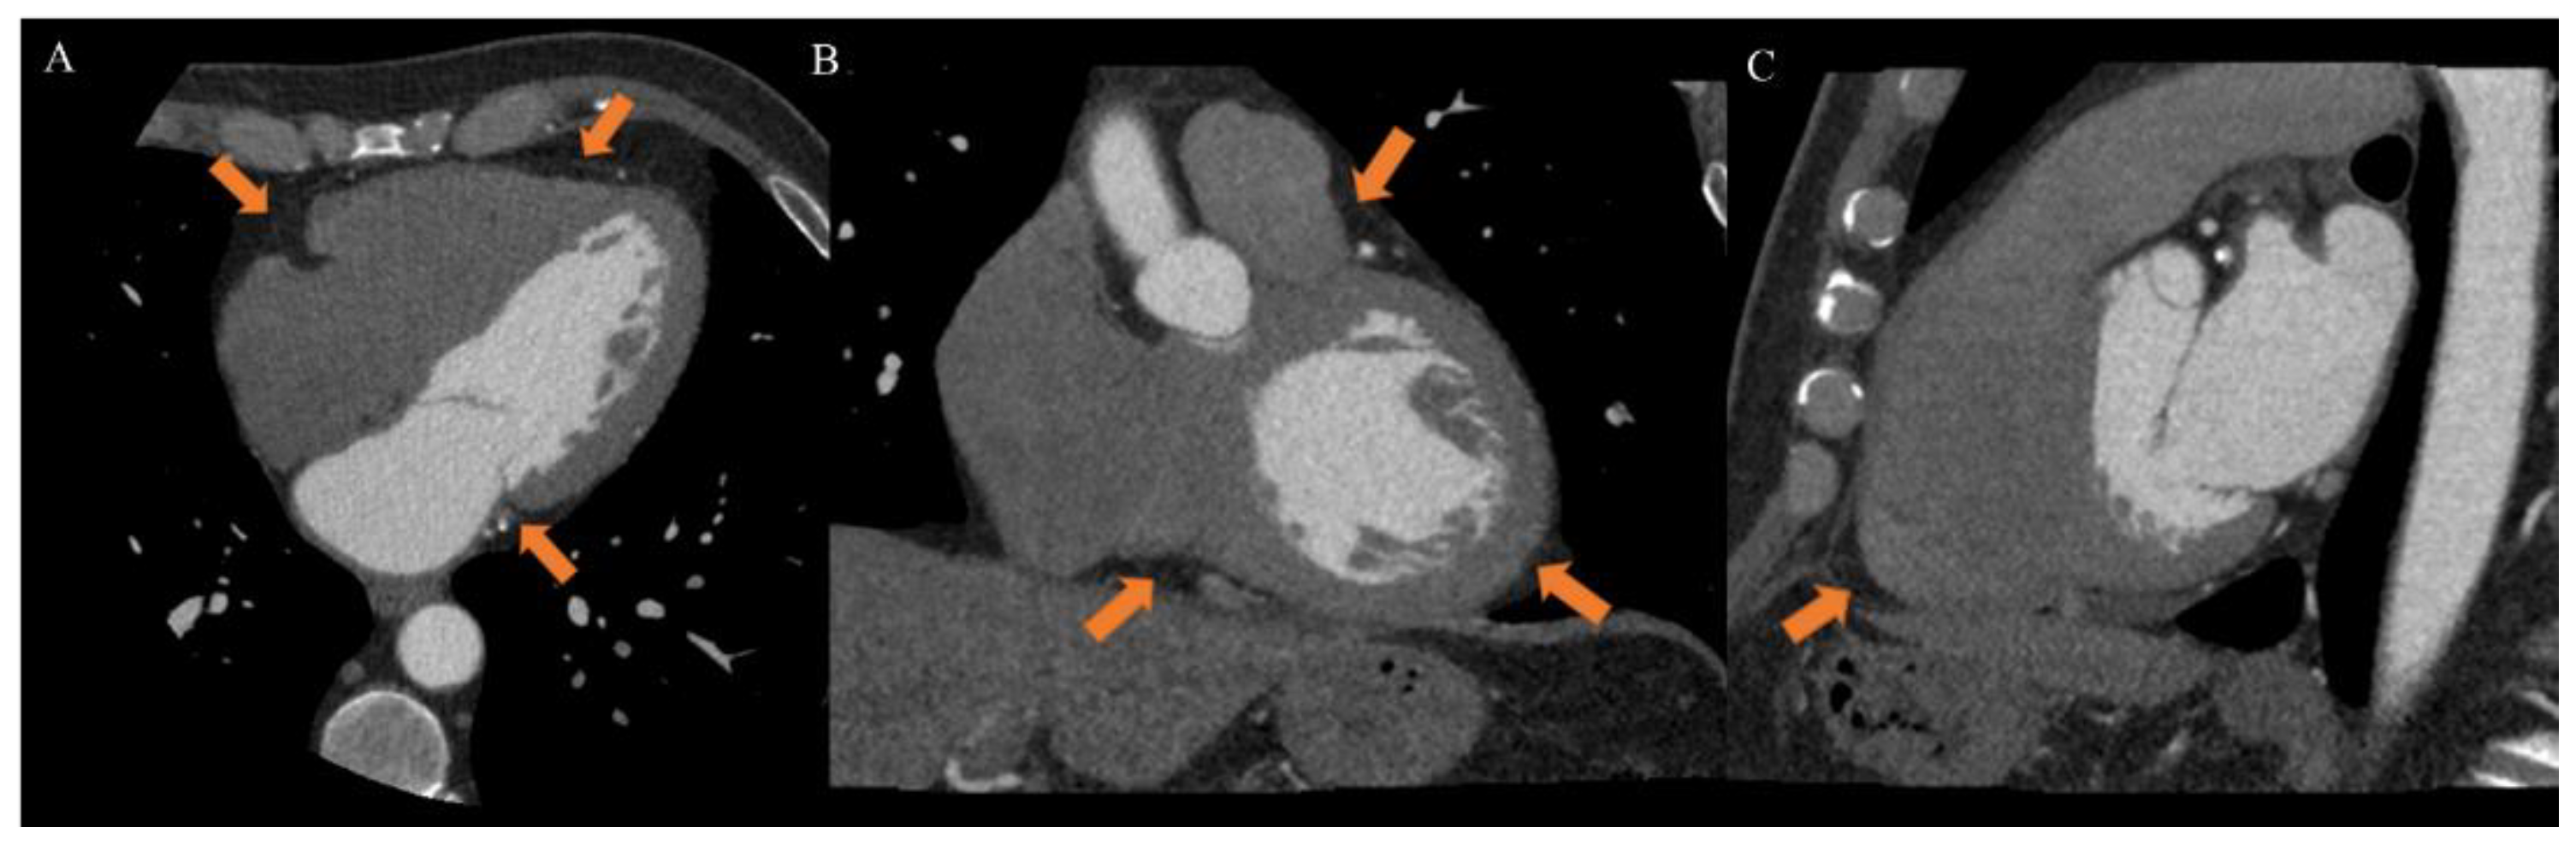

EAT is identified as the echo-free space between the outer wall of the myocardium and the visceral layer of the pericardium. According to the method first described and validated by Iacobellis et al., EAT thickness was generally measured perpendicularly on the free wall of the right ventricle at the end systole in 2–3 cardiac cycles. Maximum EAT thickness was measured at the point on the free wall of the right ventricle along the midline of the ultrasound beam, perpendicular to the aortic annulus [35]. Thickness varies among patients and usually ranges from 1 mm to 23 mm, but no definitive cut-off value has been identified [27]. For example, one study found a cut-off of 5.8 mm for predicting high-risk coronary plaques [36], while another reported that values of 9.5 mm in men and 7.5 mm in women could be considered thresholds to predict the metabolic syndrome [37]. On the other hand, CT and CMR can give also three-dimensional estimates of the overall EAT volume. In particular, the first shows higher spatial resolution and reproducibility but is limited by radiation exposure and long segmentation times, and the second is radiation-free but limited by lower spatial resolution and reproducibility, higher cost, and difficulties for obese patients [33,38]. However, thanks to different post-processing steps and without specific acquisitions, CT scans allow the calculation of EAT density, using Hounsfield Units (HU), both globally or on the perivascular coronary fat alone [26]. Moreover, the application of coronary CT angiography (CCTA) is rapidly increasing, following the ESC guidelines on the management of patients with suspicious coronary artery disease [39]. The availment of CCTA can provide data regarding coronary stenosis, plaque and characterization of EAT [5,40,41] (Figure 3).

Figure 3.

Case of a 46-year-old male patient underwent to cardiac computed tomography angiography (CCTA) for atypical chest pain. CCTA showed epicardial fat on axial ((A), arrow), coronal ((B), arrow) and sagittal ((C), arrow) planes. From Giuseppe Muscogiuri’s private archive of unpublished cardiac imaging.

EAT may be visible as a hypodense layer, with a density usually ranging from −190 to −30 HU, placed between the myocardium and the visceral pericardium. It can be quantified from different scans, most often either unenhanced scans for calcium score or CT angiographic scans, given that the EAT and pericardium are similarly visible in both, especially during the short time interval that is between contrast administration and angiographic acquisition. Therefore, adding EAT study to the output of a CT report could provide important additional information without adding to patient discomfort and radiation exposure [33]. At the same time, standard CCTA, if used only for obtaining EAT estimates, could be questioned due to the ionizing radiation exposure; however, recently Nagayama et al. proposed the use of non-gated CT, obtaining excellent concordance with gated CT but with less radiation [42]. Another limitation of EAT quantification by CT angiography is related to long segmentation times because a precise measurement is best performed on numerous small slice-thickness images; the computer software then determines EAT volume as the sum of areas of all images, accounting for slice thickness and intersection gaps. Meanwhile, several software solutions have been developed to expedite this process and rapid and fully automated algorithms for EAT volume and attenuation quantification were described [5]. La Grutta et al. conducted a study on the quantification of EAT both in coronary calcium score and CT coronary angiography image data sets comparing attenuation values, thickness and volumes obtained with these methods. The calcium score and CT coronary angiography may be used singularly in order to reduce the radiation dose, a systematic comparison of EAT assessment was useful to define their interchangeability. The image data sets may be equally employed for EAT quantification, but an underestimation of volume is found with CT coronary angiography acquisition even after post-contrast attenuation adjustment [43].